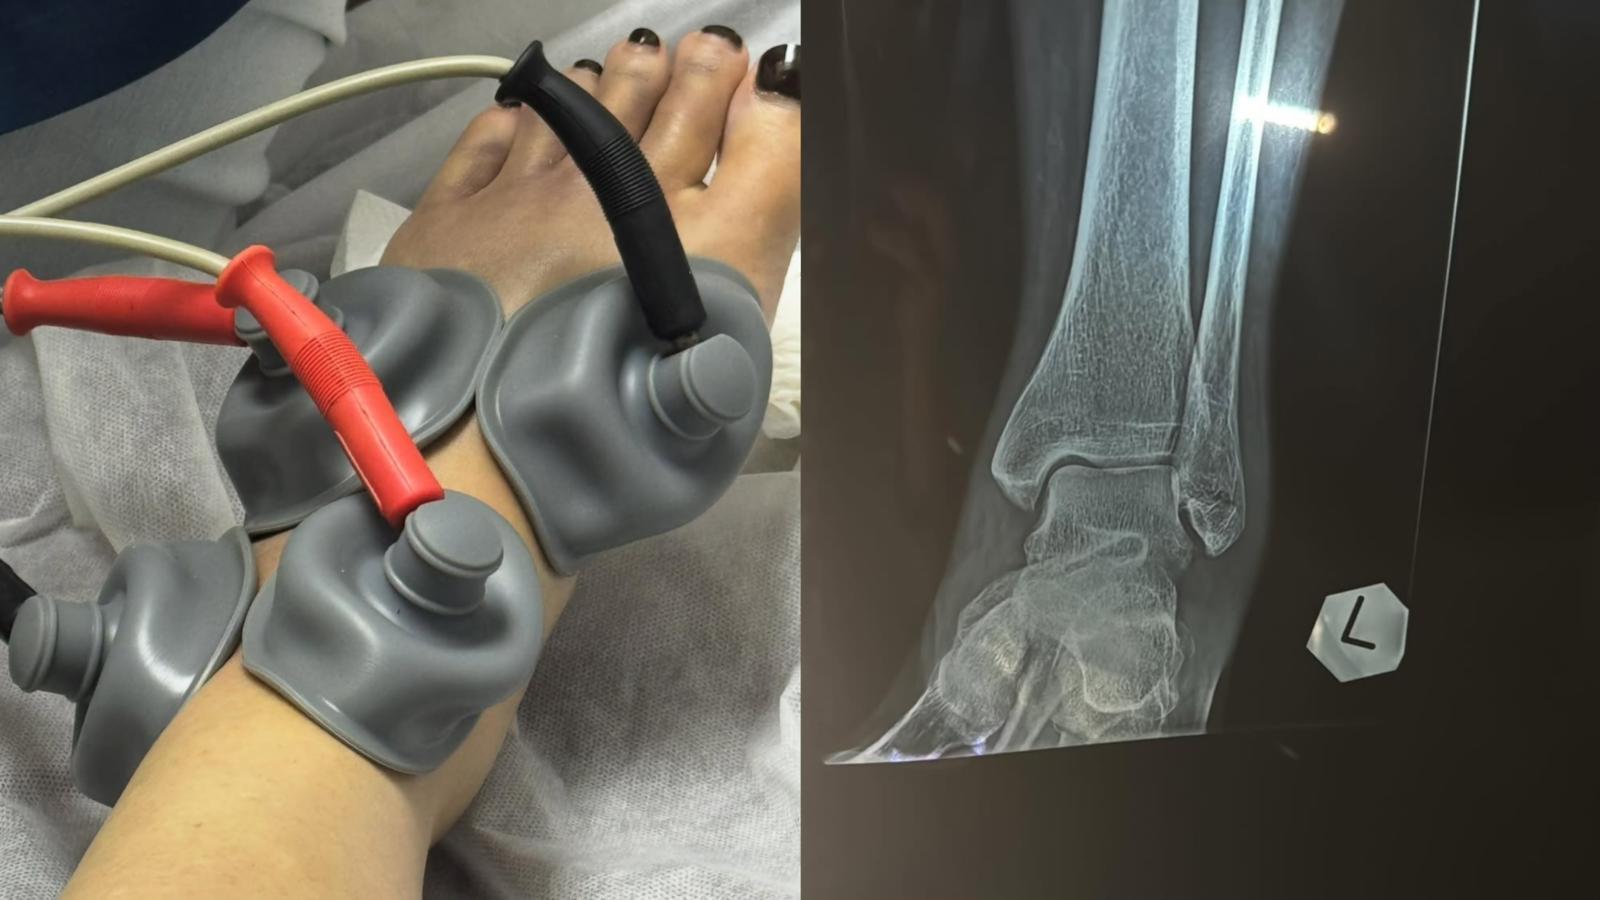

余安安在上年播出的劇集《家族榮耀之繼承者》演戴綺婷一角,獲得觀眾大讚演技出色,最近她甚少參與幕前演出。余安安前日(8日)在社交網自爆兩星期前人生第一次拗柴,後來情況嚴重到骨裂,需要接受中西合璧治療。另外她還上載一系列腳傷情況的照片,她需要靠雙手撐住枴杖行路,而左腳要用護具固定。

余安安發文指拗柴原本以為拗柴的情況並不是太嚴重,所以當晚忍痛陪伴孫仔去看燈飾。她續說:「再過多兩日又覺得唔多妥去照埋X-Ray,原來骨裂咗,不幸中之大幸係冇移位,要買對超貴嘅boot着,慶幸係左腳,右腳最近仲可以揸到車。」